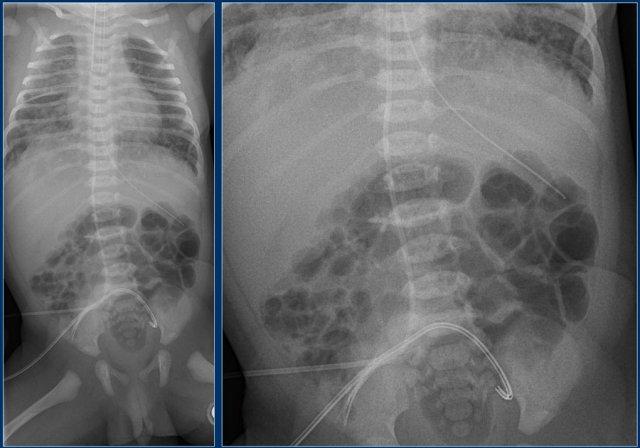

Các phát hiện bao gồm:

- Đặt sai vị trí đường truyền động mạch rốn, bị gấp khúc trong lòng động mạch chủ bụng.

Đường truyền động mạch rốn (4)

Hãy quan sát kỹ hình ảnh trước.

Sau đó tiếp tục đọc.

- Đường truyền động mạch rốn ở vị trí quá sâu, đầu catheter nằm tại quai động mạch chủ.

- Đường truyền tĩnh mạch rốn với đầu catheter nằm trong nhánh tĩnh mạch cửa phải.